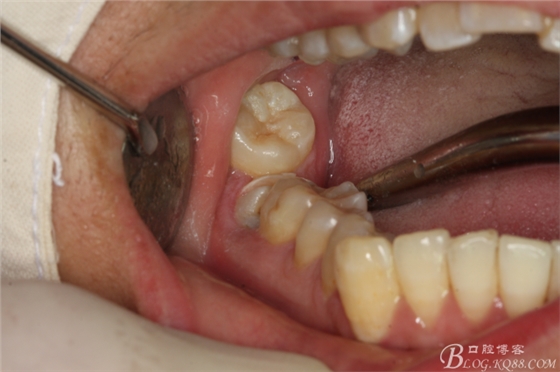

圖20.金剛砂車(chē)針片切44牙冠、消除鄰牙阻力

圖21.片切完成的44牙冠